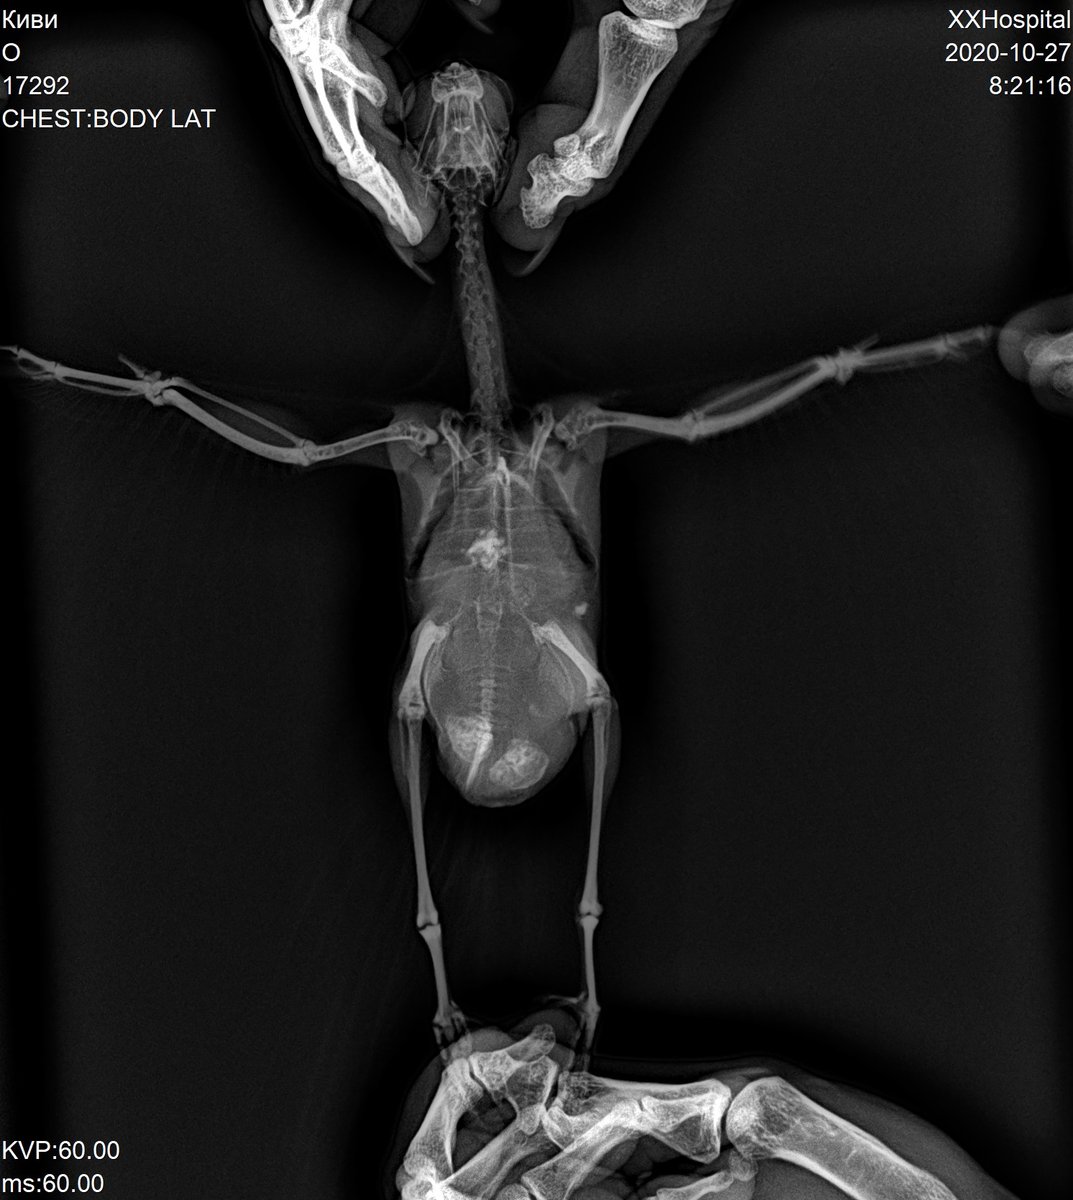

Застряли лопнувшие яйца. Самка какарик.

10. Какие симптомы Вас насторожили? Как они развивались? сидела нахохлившись и тяжело дышала. Отвезли к орнитологу. Сделали рентген и УЗИ. Оказалось внутри застряло 2 лопнувших яйца. Жидкость в брюшной полости. Жидкость откачали 7 мл - зеленая. Назначили Синулокс 1/4 таблетки с 0,5мл воды 2 раза в день. Через 5 дней назначили другой прием, снова сделали рентген. Жидкость снова собралась, откачали 5 мл. Добавили Карсил 35мг по 1/4 растолочь, развести в 1 мл воды давать по 2 м этого раствора. Назначили следующий прием через 7 дней - осмортели, сазалт если жидкость снова будет скапливаться привозить и откачивать. Прошло 5 дней я вижу что брюшко снова раздуто

Это последний ренген

17292_3.jpg